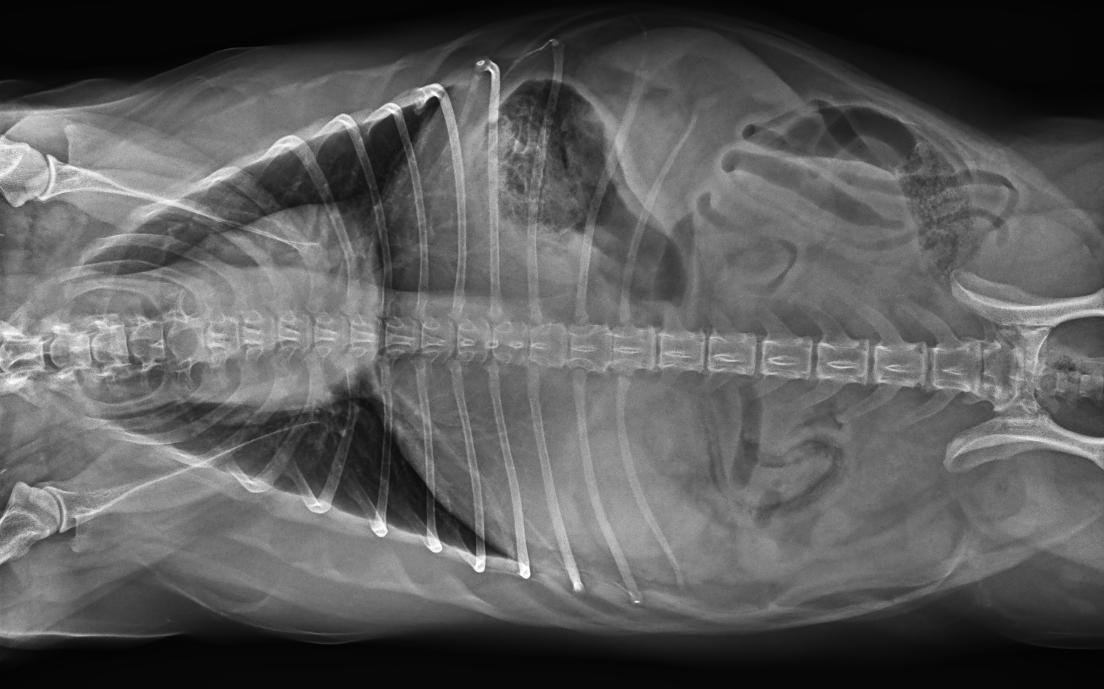

精致小巧的機身設(shè)計與靈活緊湊的機架結(jié)構(gòu),大大節(jié)約了占地面積,滿足多種安裝條件。

● 占地面積小,滿足多種安裝條件